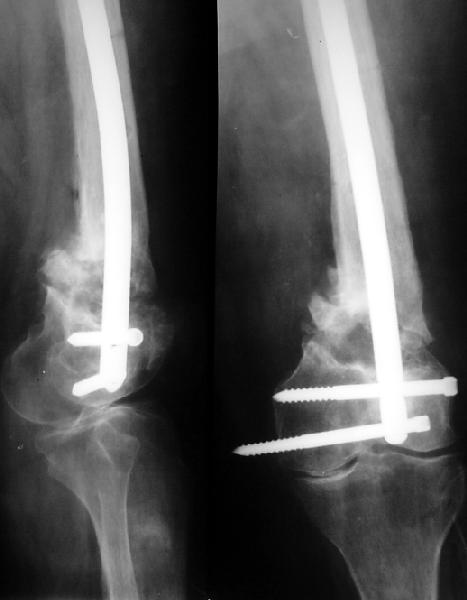

Пример подобного ложного сустава в приложении.

На сегодня есть имплантаты с куда более продвинутой дистальной фиксацией.